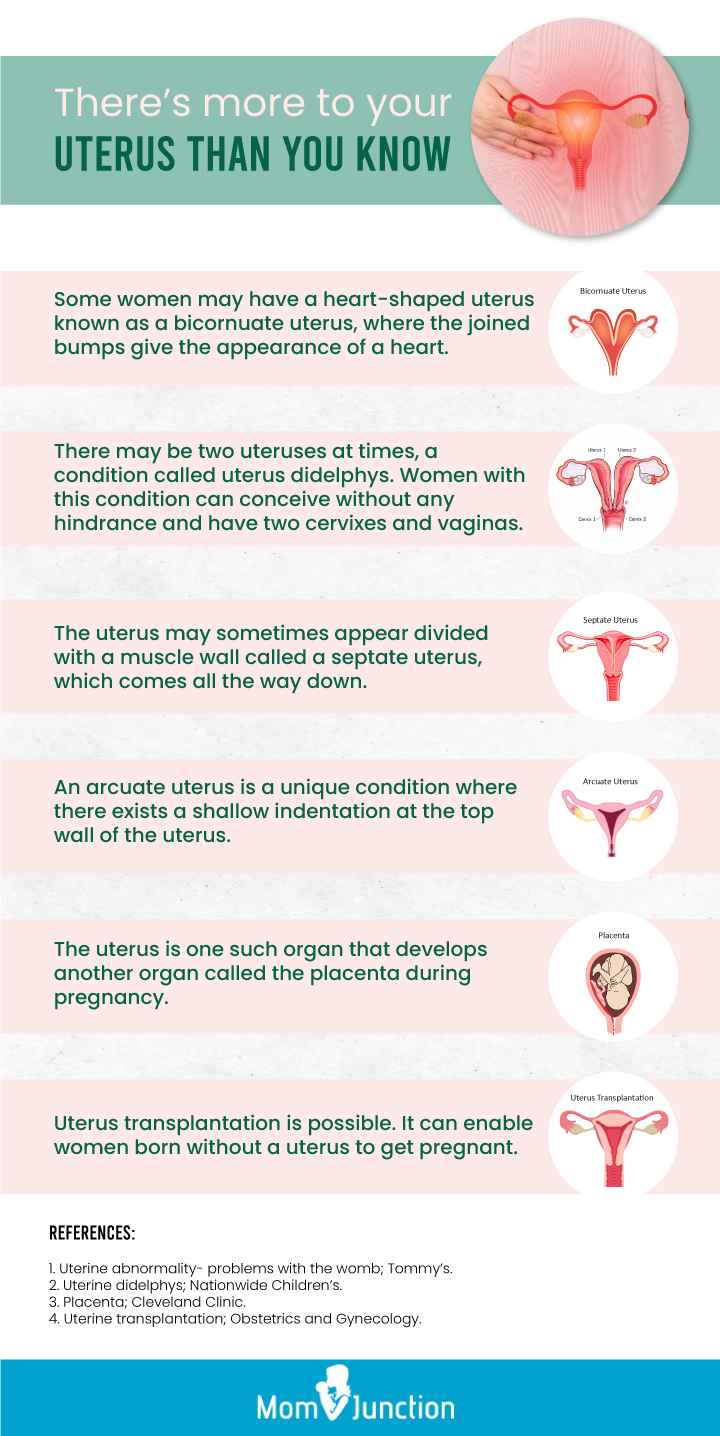

Uterus Anatomy Function Inverted Tipped Transplantation